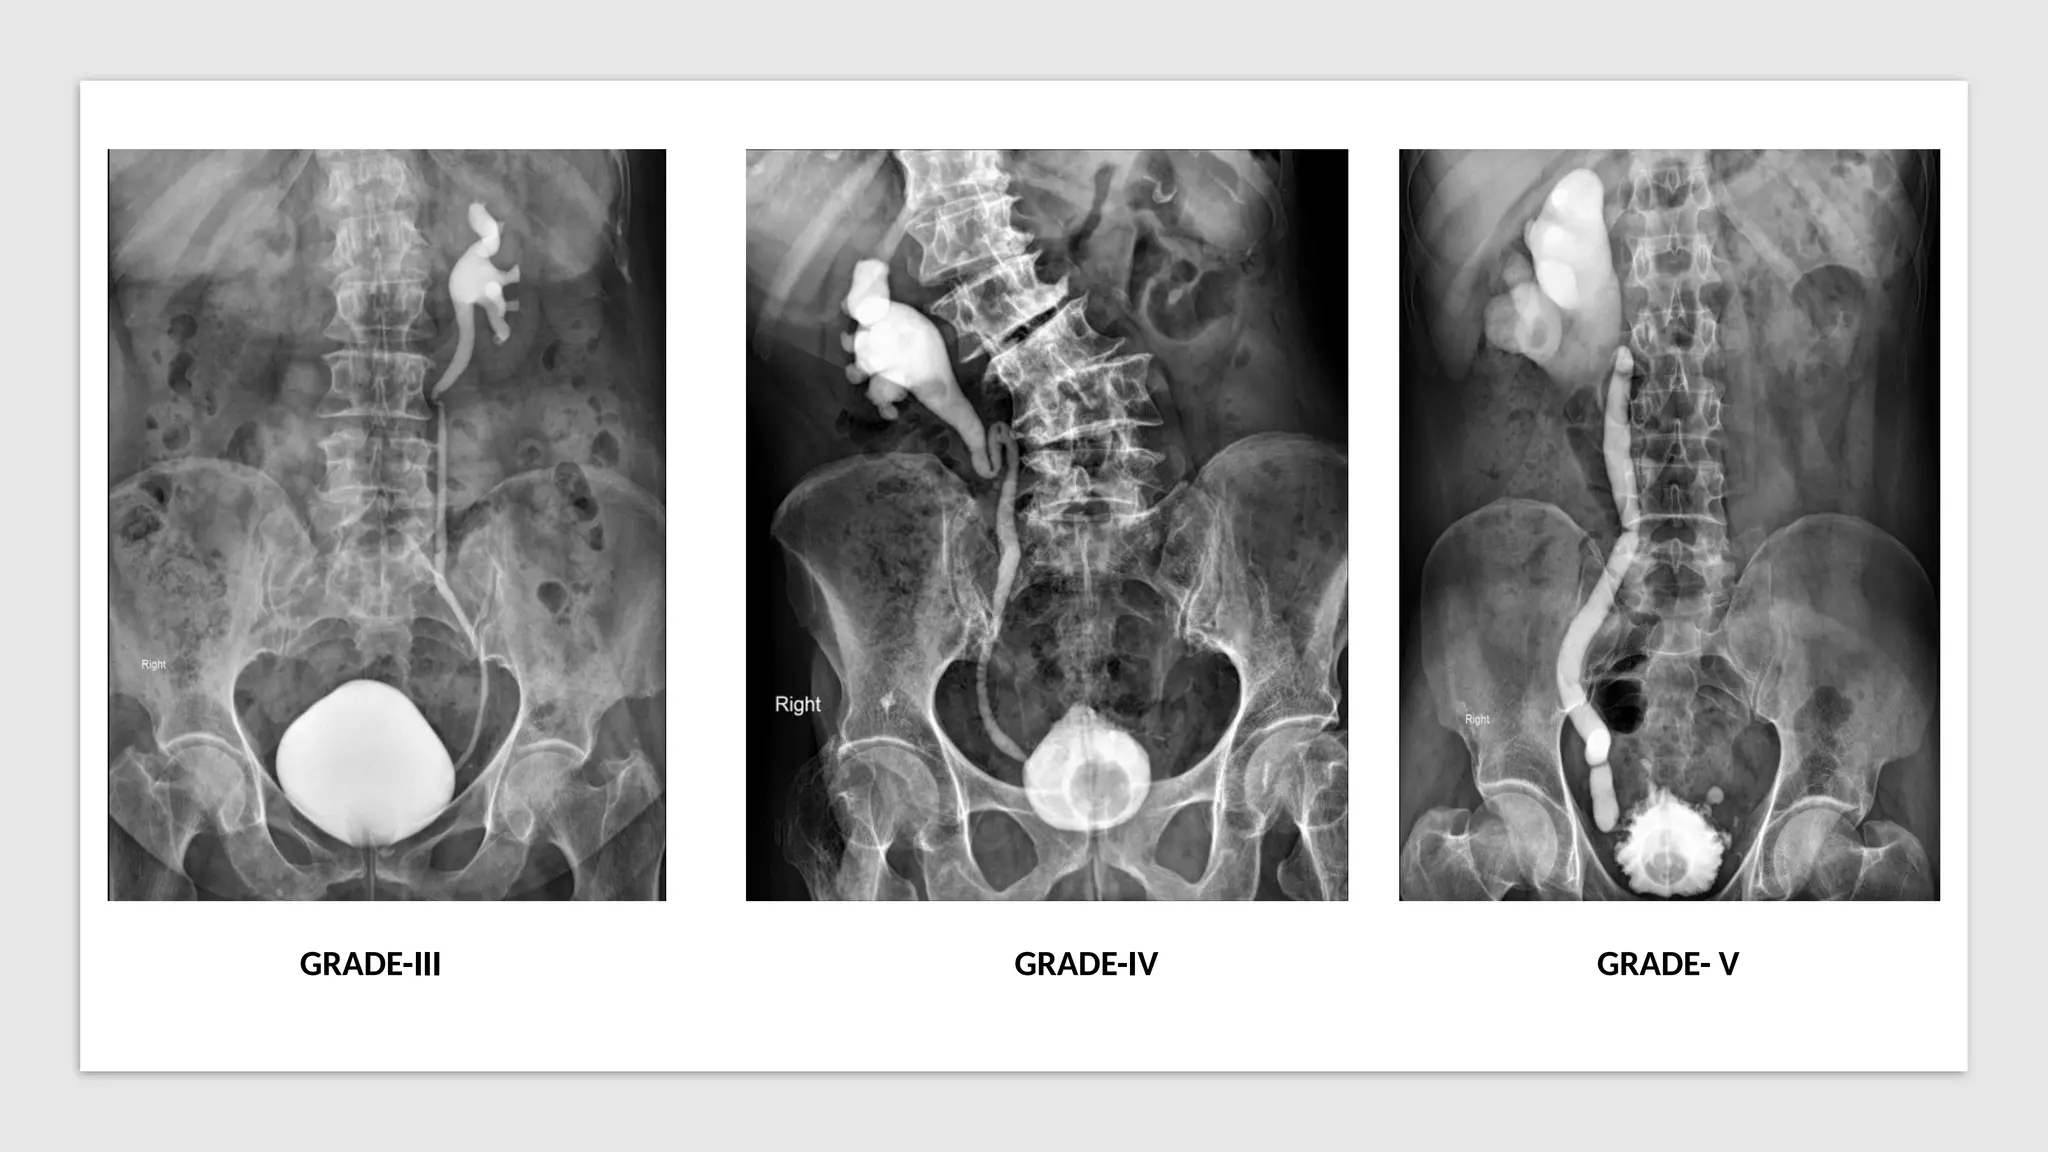

Vesicoureteric reflux (VUR) grading according to the

height of reflux up the ureters and degree of

dilatation of the ureters:

• Grade 1: reflux limited to the ureter

• Grade 2: reflux up to the renal pelvis

• Grade 3: mild dilatation of ureter and

pelvicalyceal system

• Grade 4

• tortuous ureter with moderate dilatation

• blunting of fornices but preserved papillary

impressions

• Grade 5

• tortuous ureter with severe dilatation of

ureter and pelvicalyceal system

• loss of fornices and papillary impressions

GRADE-III GRADE-IV GRADE- V